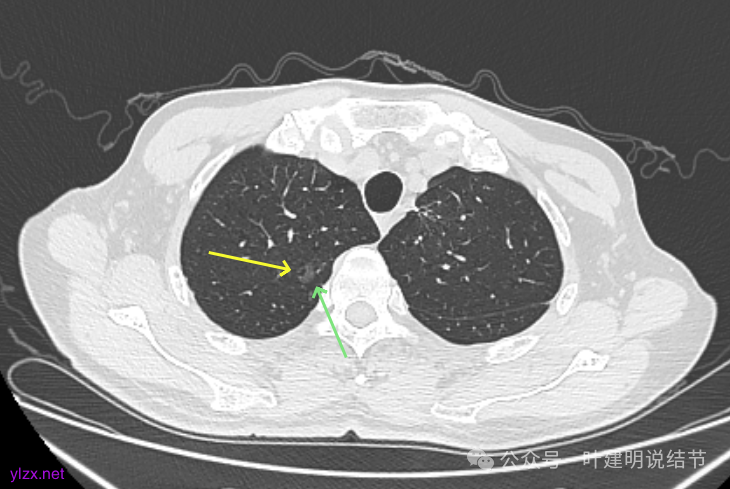

再看2024年9月的:

右上的较前略增大,且有空泡征较豙明显些,肿瘤的成分仍是纯磨密度。

左上病灶也是较为纯的,边缘不光滑,大小似乎略大一点点,不太显著。